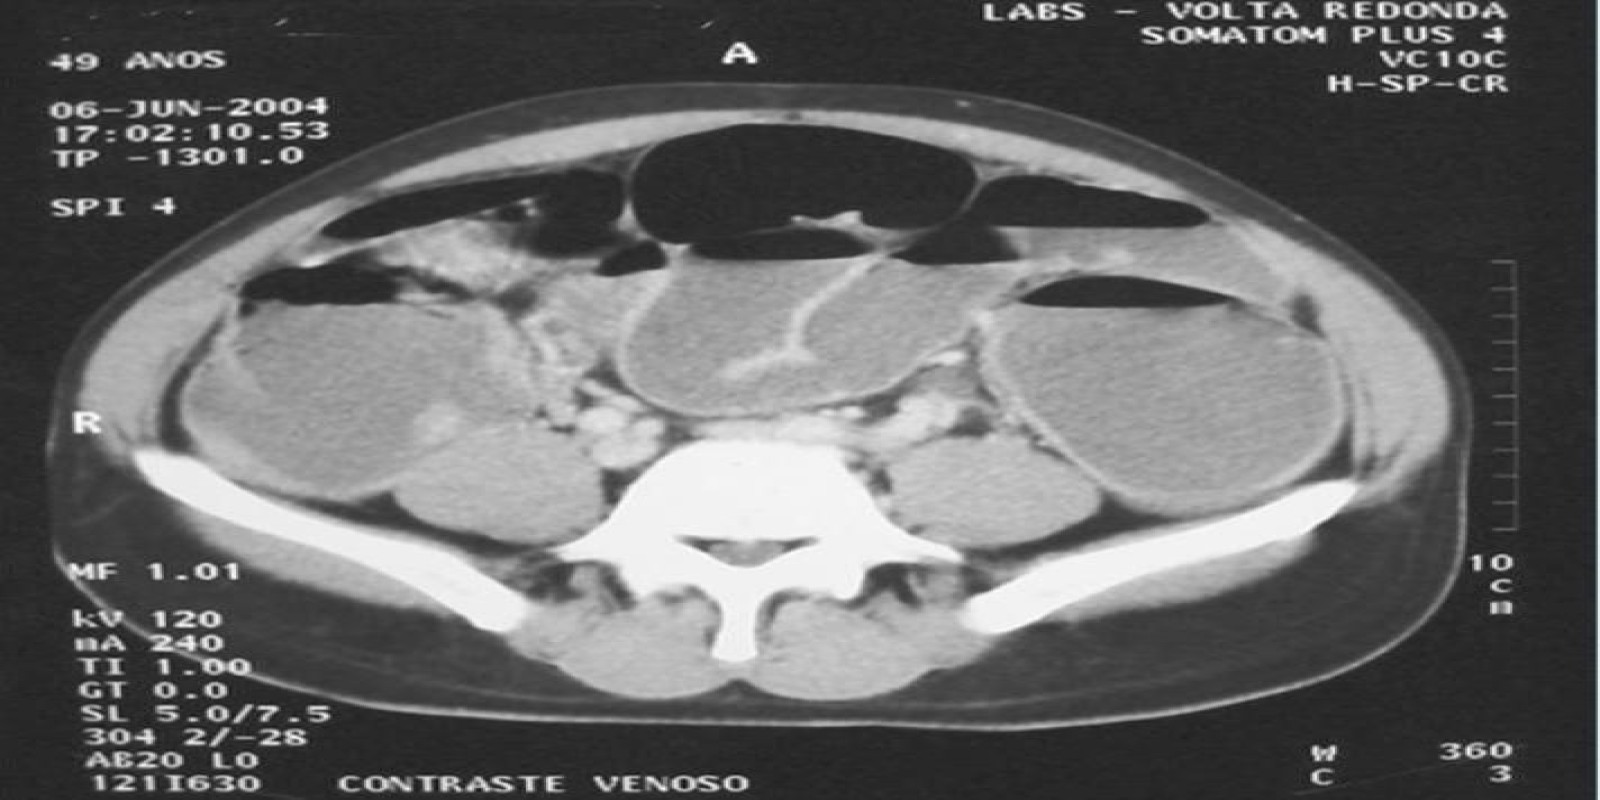

Caso Código 260A de Obstrução Intestinal do Cólon

Cod.: 260A